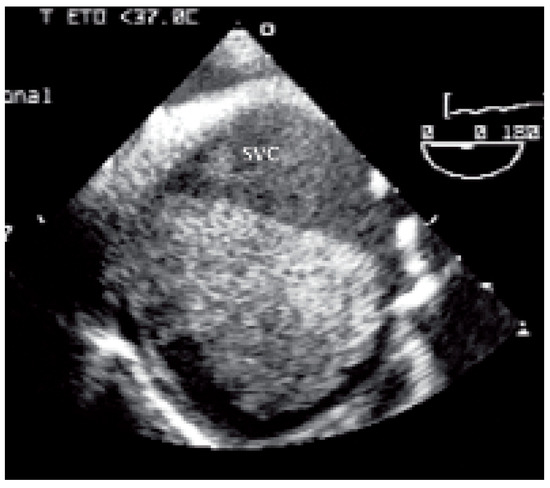

Valve Prosthesis in the Tricuspid Position: An Useasy Relationship

by P. Trigo Trindade, J. Sierra and C. Vuille

Cardiovasc. Med. 2006, 9(4), 167; https://doi.org/10.4414/cvm.2006.01163 - 28 Apr 2006

Case report. A27-year-old woman from Madagascar was referred to our institution because of right heart failure [...] Full article